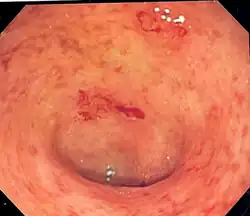

| Endoscopic image of a colon affected by ulcerative colitis. The internal surface of the colon is blotchy and broken in places. Mild-moderate disease. | |

Endoscopic

The best test for the diagnosis of ulcerative colitis remains endoscopy, which is the examination of the internal surface of the bowel using a flexible camera. Initially, a flexible sigmoidoscopy may be completed to establish the diagnosis.[73] The physician may elect to limit the extent of the initial exam if severe colitis is encountered to minimize the risk of perforation of the colon. However, a complete colonoscopy with entry into the terminal ileum should be performed to rule out Crohn's disease and assess the extent and severity of the disease.[73] Endoscopic findings in ulcerative colitis include: erythema (redness of the mucosa), friability of the mucosa, superficial ulceration, and loss of the vascular appearance of the colon. When present, ulcerations may be confluent. Pseudopolyps may be observed.[74]

Ulcerative colitis is usually continuous from the rectum, with the rectum almost universally involved. Perianal disease is rare. The degree of involvement endoscopically ranges from proctitis (rectal inflammation) to left-sided colitis (extending to the descending colon) to extensive colitis (extending proximal to the descending colon).[14]